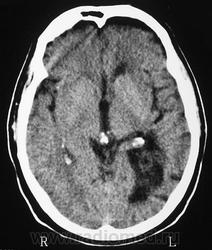

ГМ. Субэпендимома 2. +

Субэпендимома